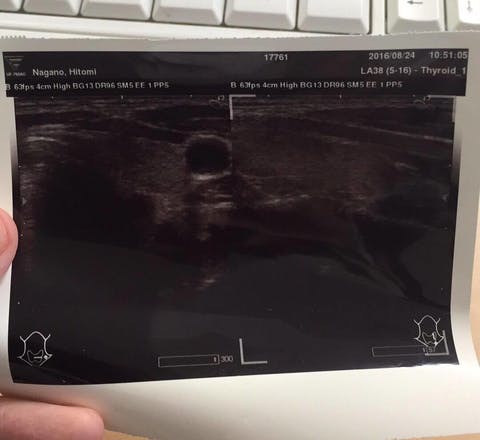

結果です。

「がん、ないよ」

甲状腺の左葉、真ん中に確かにあった、がんは、すっかり消えてなくなっていました!!

「うそ~!!消えたってことですか?」

びっくりしました。こんなことって本当にあるんですね。

大きくなっていなきゃいいやって思っていましたが、まさか消えているなんて。